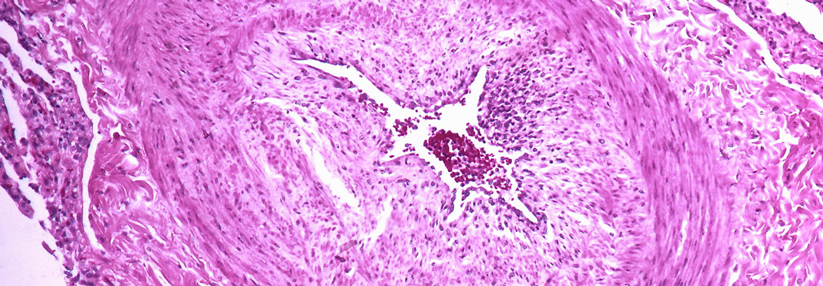

Wahrscheinlich gibt es einen speziellen pulmonalvaskulären Phänotyp der COPD, der typischerweise ohne starke Atemflusseinschränkung daherkommt, aber eine ausgeprägte Hypoxämie und Diffusionskapazität zeigt. „Diese Patienten haben keine schwere Bronchialerkrankung, sondern eher ein kardiovaskuläres Problem“, so Prof. Krüger. „Wenn Sie bei ihnen eine Spiroergometrie machen, ist die Belastbarkeit nicht pulmonal limitiert, sondern kardial.“ Die vaskulären Veränderungen sehen ähnlich aus wie bei der idiopathischen pulmonalen Hypertonie und das Mortalitätsrisiko ist stärker durch die PH geprägt als durch die FEV1.

Es gibt wohl einen pulmonalvaskulären Phänotyp der COPD